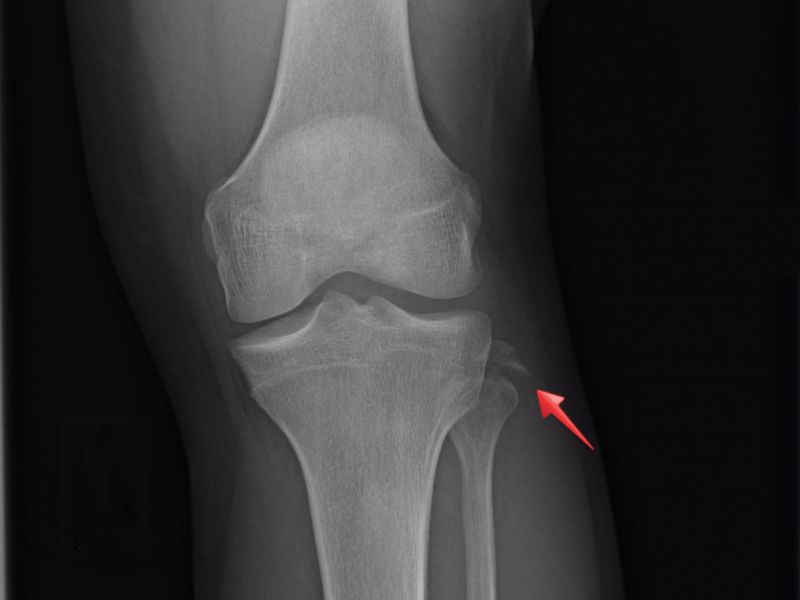

Answer: Avulsion fracture of the fibular styloid process